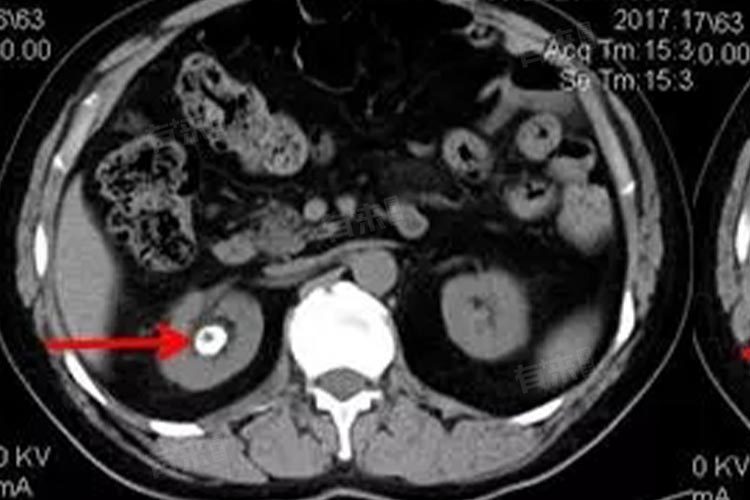

2、定期复查监测:定期进行肾脏超声、腹部X线或CT等检查,密切观察结石大小、位置及数量变化。一般建议每3-6个月复查一次,若出现腰腹部疼痛、血尿、排尿困难等症状,应及时就医。通过定期复查,医生可根据结石情况调整治疗方案,及时采取干预措施,防止结石增大或引发严重并发症。